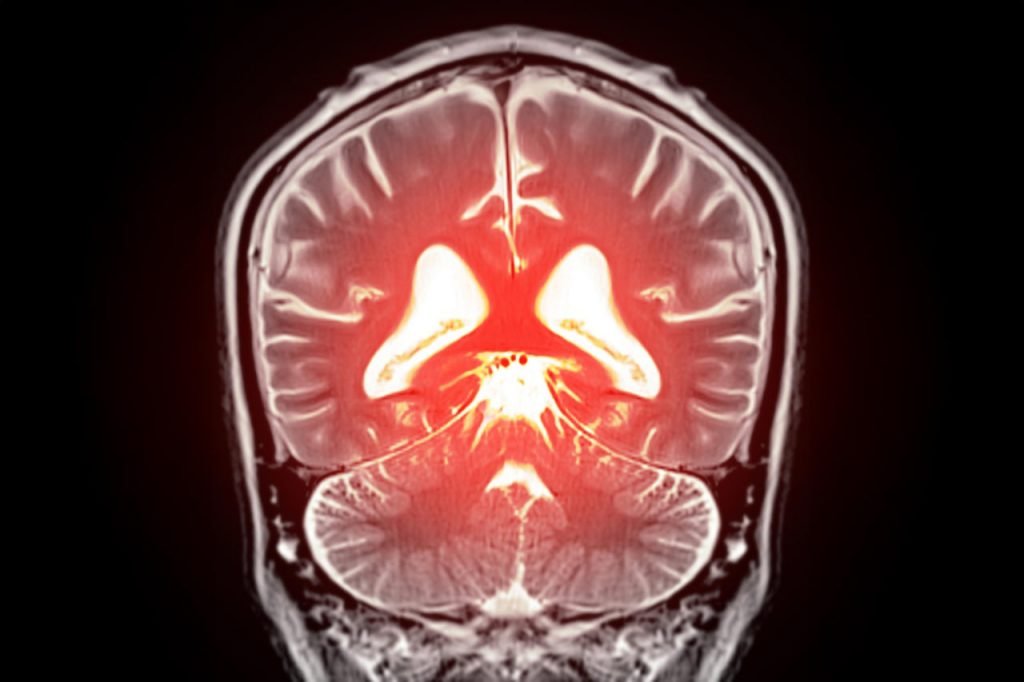

کشف امیدوارکننده برای درمان زوال عقل: کنترل یک پروتئین خاص می‌تواند فشار خون مغز را اصلاح کند

مطالعه جدیدی نشان می‌دهد که بخشی از زوال عقل می‌تواند ناشی از اختلال در جریان خون مغز باشد. پژوهشگران در این تحقیق متوجه شده‌اند که از بین رفتن یک نوع لیپید کلیدی باعث می‌شود رگ‌های خونی بیش از حد فعال شوند، گردش خون مختل شود و بافت مغز در نهایت اکسیژن و مواد غذایی را دریافت نکند. سپس وقتی این مولکولِ از دست‌رفته دوباره به سیستم برگردانده شده، جریان طبیعی خون نیز به حالت عادی خود برگشته است.

دانشمندان «دانشکده پزشکی رابرت لارتر دانشگاه ورمونت» در این تحقیق به جزئیات جدیدی از نحوه کنترل گردش خون در مغز و راه‌هایی برای معکوس‌کردن مشکلات عروقی اشاره کرده‌اند. به‌طور کلی این تحقیق نشان داده که جایگزین کردن یک فسفولیپید از دست رفته در جریان خون، می‌تواند روند گردش خون در مغز را طبیعی کند و به کاهش علائم مرتبط با زوال عقل کمک می‌کند.